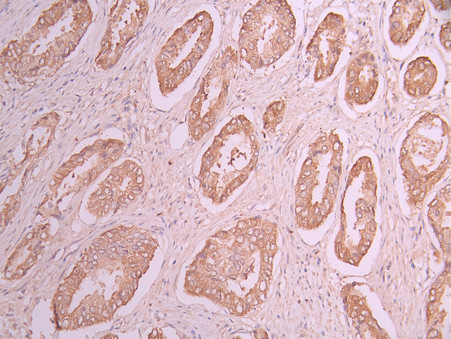

IHC image of CSB-RA903387A0HU diluted at 1:100 and staining in paraffin-embedded human prostate cancer performed on a Leica BondTM system. After dewaxing and hydration, antigen retrieval was mediated by high pressure in a citrate buffer (pH 6.0). Section was blocked with 10% normal goat serum 30min at RT. Then primary antibody (1% BSA) was incubated at 4°C overnight. The primary is detected by a Goat anti-rabbit polymer IgG labeled by HRP and visualized using 0.05% DAB.